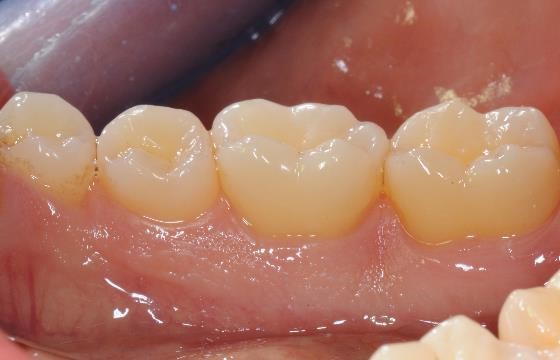

16/22 - Clinical situation 12 months post-operative. Lingual view.

Deep intrabony defects treated using Straumann® Emdogain® - Dr. M. Stefanini